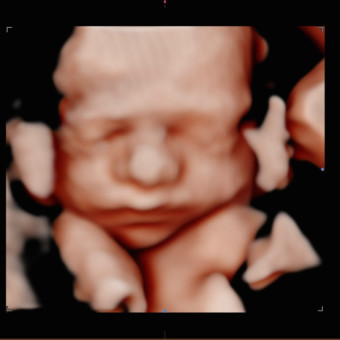

River Grey Wilkerson

Chelsae & Kyle Wilkerson

Roxboro, NC

December 12, 2025

We are so excited to be adding this little man to our family! Thanks for being a part of our village!